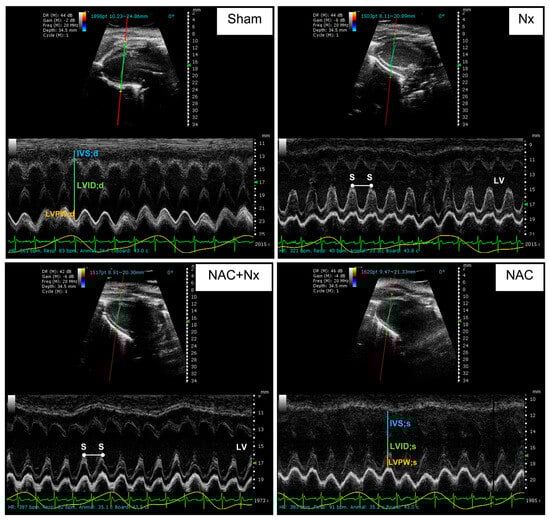

| Parameter | Sham | NX | NAC+NX | NAC |

|---|---|---|---|---|

| HR (bpm) | 355.9 ± 19.3 | 365.2 ± 23.5 | 391 ± 24.6 | 365.9 ± 28.9 |

| IVS;d (mm) | 0.9 ± 0.1 | 1.1 ± 0.2 | 1.1 ± 0.3 | 1.1 ± 0.3 |

| LVID;d (mm) | 6.9 ± 0.8 | 6.7 ± 0.7 | 6 ± 0.6 | 6.8 ± 0.7 |

| LVPW;d (mm) | 1.5 ± 0.3 | 1.2 ± 0.2 | 1.3 ± 0.3 | 1.2 ± 0.1 |

| FS (%) | 57.8 ± 14.2 | 38.5 ± 7.9 * | 52 ± 9.9 *** | 52.1 ± 5.5 |

| EDV (µL) | 253.5 ± 65.9 | 236.2 ± 52.4 | 181.7 ± 39.9 | 245.6 ± 52.9 |

| ESV (µL) | 42.4 ± 37.1 | 78.2 ± 28.3 | 35.3 ± 17.5 *** | 48.3 ± 18.8 |

| EF (%) | 84.3 ± 10.1 | 66.5 ± 9.5 *,** | 80.1 ± 9.6 *** | 81.1 ± 4.6 |

| SV (µL) | 211.1 ± 42.9 | 158 ± 44.1 | 146.4 ± 36.2 * | 197.3 ± 36 |

| CO (mL/min) | 76.7 ± 17.7 | 57.2 ± 15.4 | 57.5 ± 15.1 | 72 ± 14 |